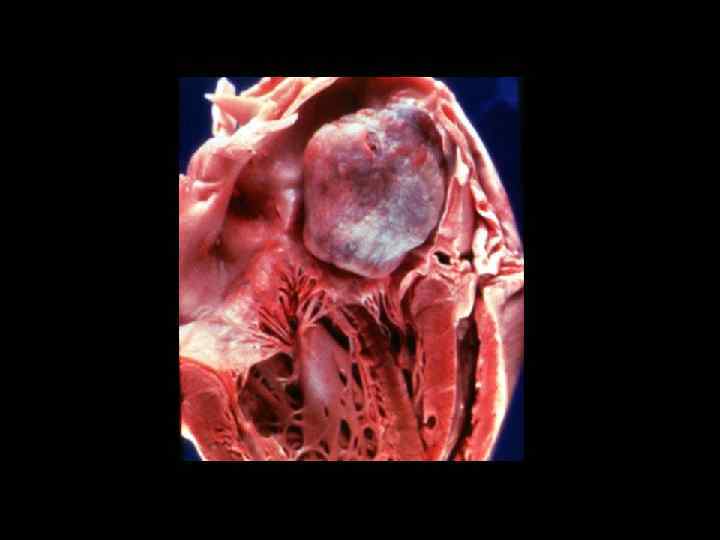

ОСТРАЯ РЕВМАТИЧЕСКАЯ ЛИХОРАДКА «ГРАНУЛЕМЫ АШОФФА» участок фибриноидного некроза, окруженный воспалительными клетками РУБЦОВАЯ ТКАНЬ ПРОГРЕССИРУЮЩАЯ ОСТРАЯ РЕВМАТИЧЕСКАЯ ЛИХОРАДКА «ГРАНУЛЕМЫ АШОФФА» участок фибриноидного некроза, окруженный воспалительными клетками РУБЦОВАЯ ТКАНЬ ПРОГРЕССИРУЮЩАЯ ДЕФОРМАЦИЯ НАРУШЕНИЕ ФУНКЦИИ ОДНОГО ИЛИ НЕСКОЛЬКИХ КЛАПАНОВ

ОСЛОЖНЕНИЯ Растяжение левого предсердия пристеночные тромбы мерцательная аритмия ОСЛОЖНЕНИЯ Растяжение левого предсердия пристеночные тромбы мерцательная аритмия